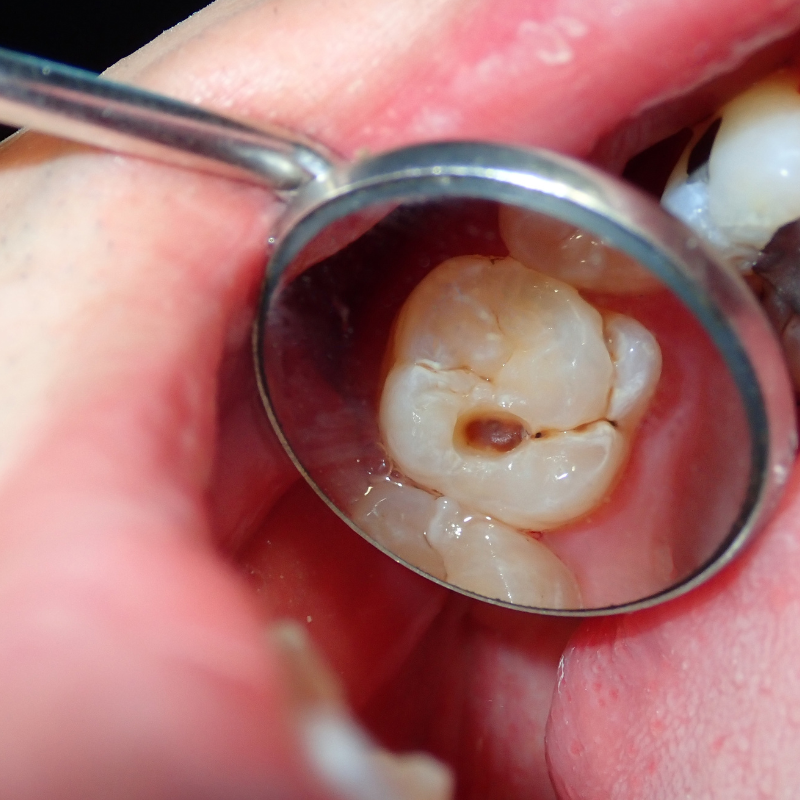

補牙過程中,醫師會清除蛀牙,並使用材料填補缺損。這個過程可能讓牙齒短暫變得比較敏感,常見原因包括:

1. 牙齒受到刺激(最常見)

清除蛀牙時,牙齒內部的神經(牙髓)可能受到輕微刺激

2. 蛀牙本來就比較深

如果蛀牙接近神經,即使已經補好

➡ 牙齒仍可能出現幾天到幾週的敏感期